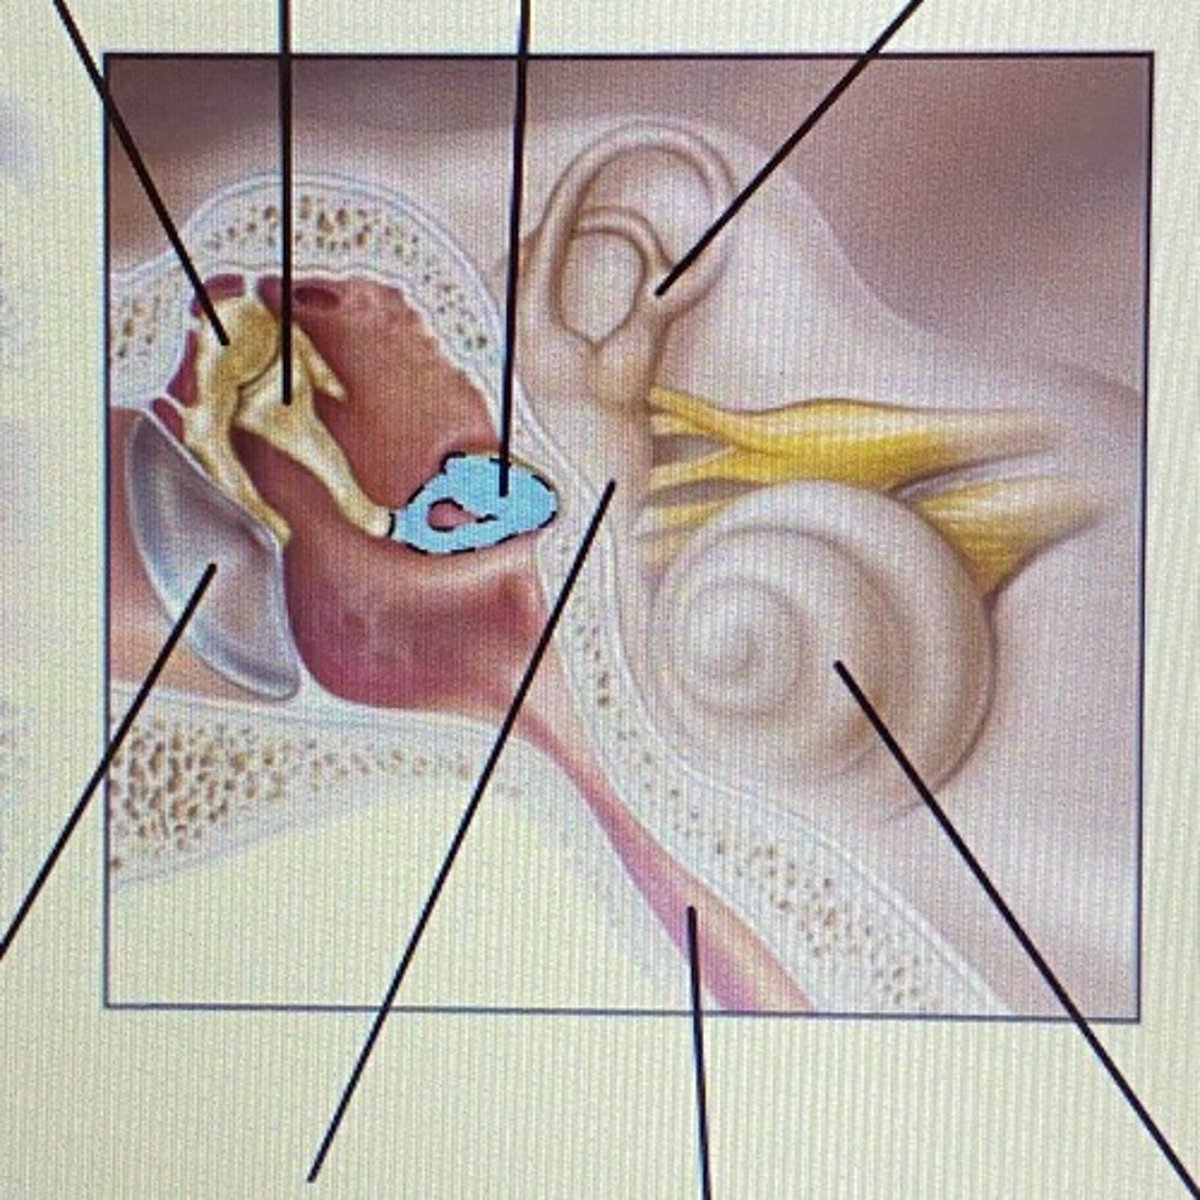

auricle

External Acoustic Meatus

vestibule

-functions in balance and equilibrium

Vestibulocochlear Nerve

- cranial nerve 8

Stapes

Incus

Malleus

Tympanic Membrane

pharyngotympanic tube

external ear

middle ear